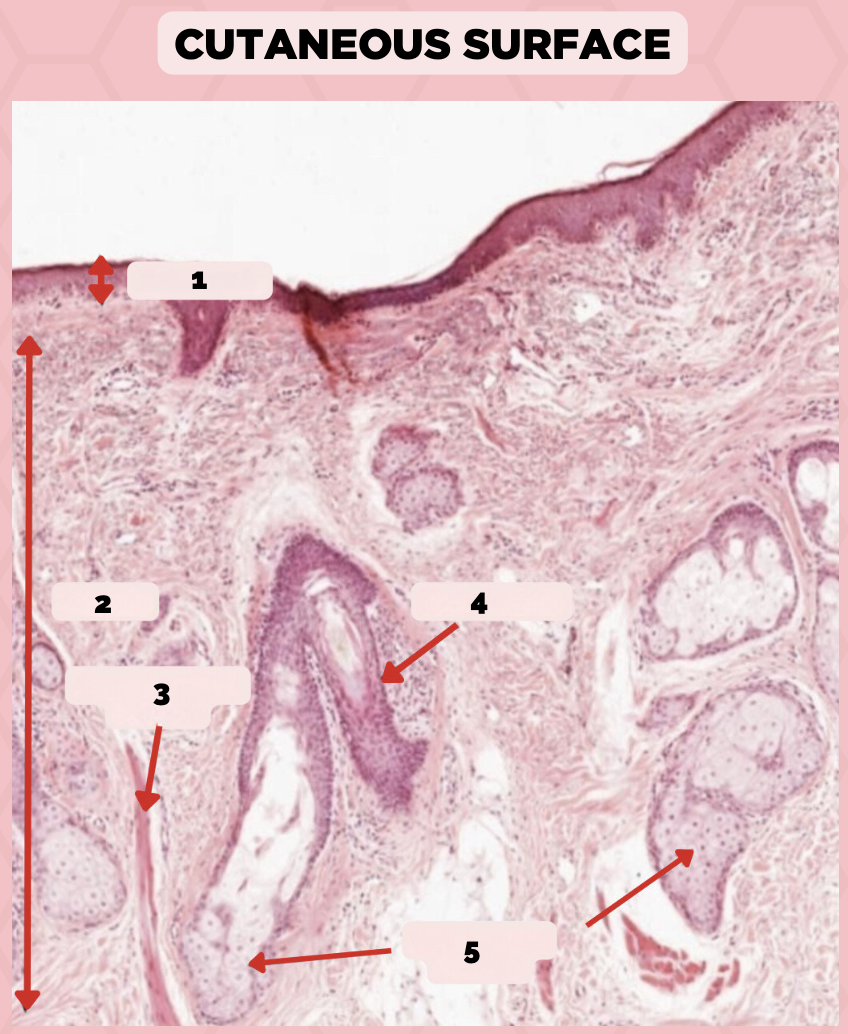

Lip

What specimen is being showed in the picture?

Epidermis

Identify the structure labeled as 1.

Dermis

Identify the structure labeled as 2.

Arrector Pilli Muscle

Identify the structure labeled as 3.

Hair Follicle

Identify the structure labeled as 4.

Sebaceous Glands

Identify the structure labeled as 5.